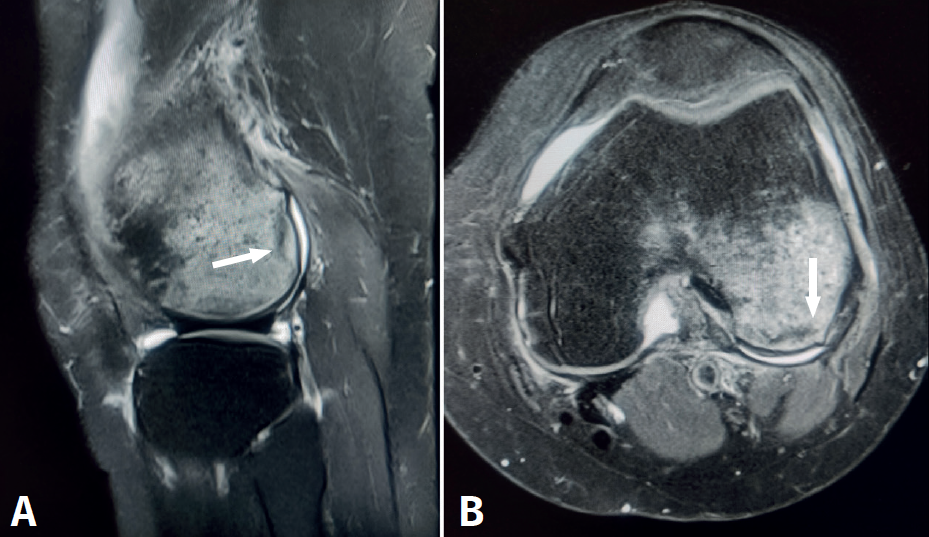

- Mecanismo de pivotaje, asociado frecuentemente a roturas del ligamento cruzado anterior, con edema óseo en el cóndilo femoral lateral y la zona posterior de los platillos tibiales (Figura 7).

Figura 7. Resonancia magnética de rodilla, cortes sagitales, con rotura del ligamento cruzado anterior. A: secuencia potenciada en T1, se aprecia edema óseo con señal hipointensa en el cóndilo femoral externo y en la zona posterior del platillo tibial; B: secuencia potenciada en T2, se aprecia edema óseo con la misma distribución, pero señal hiperintensa.